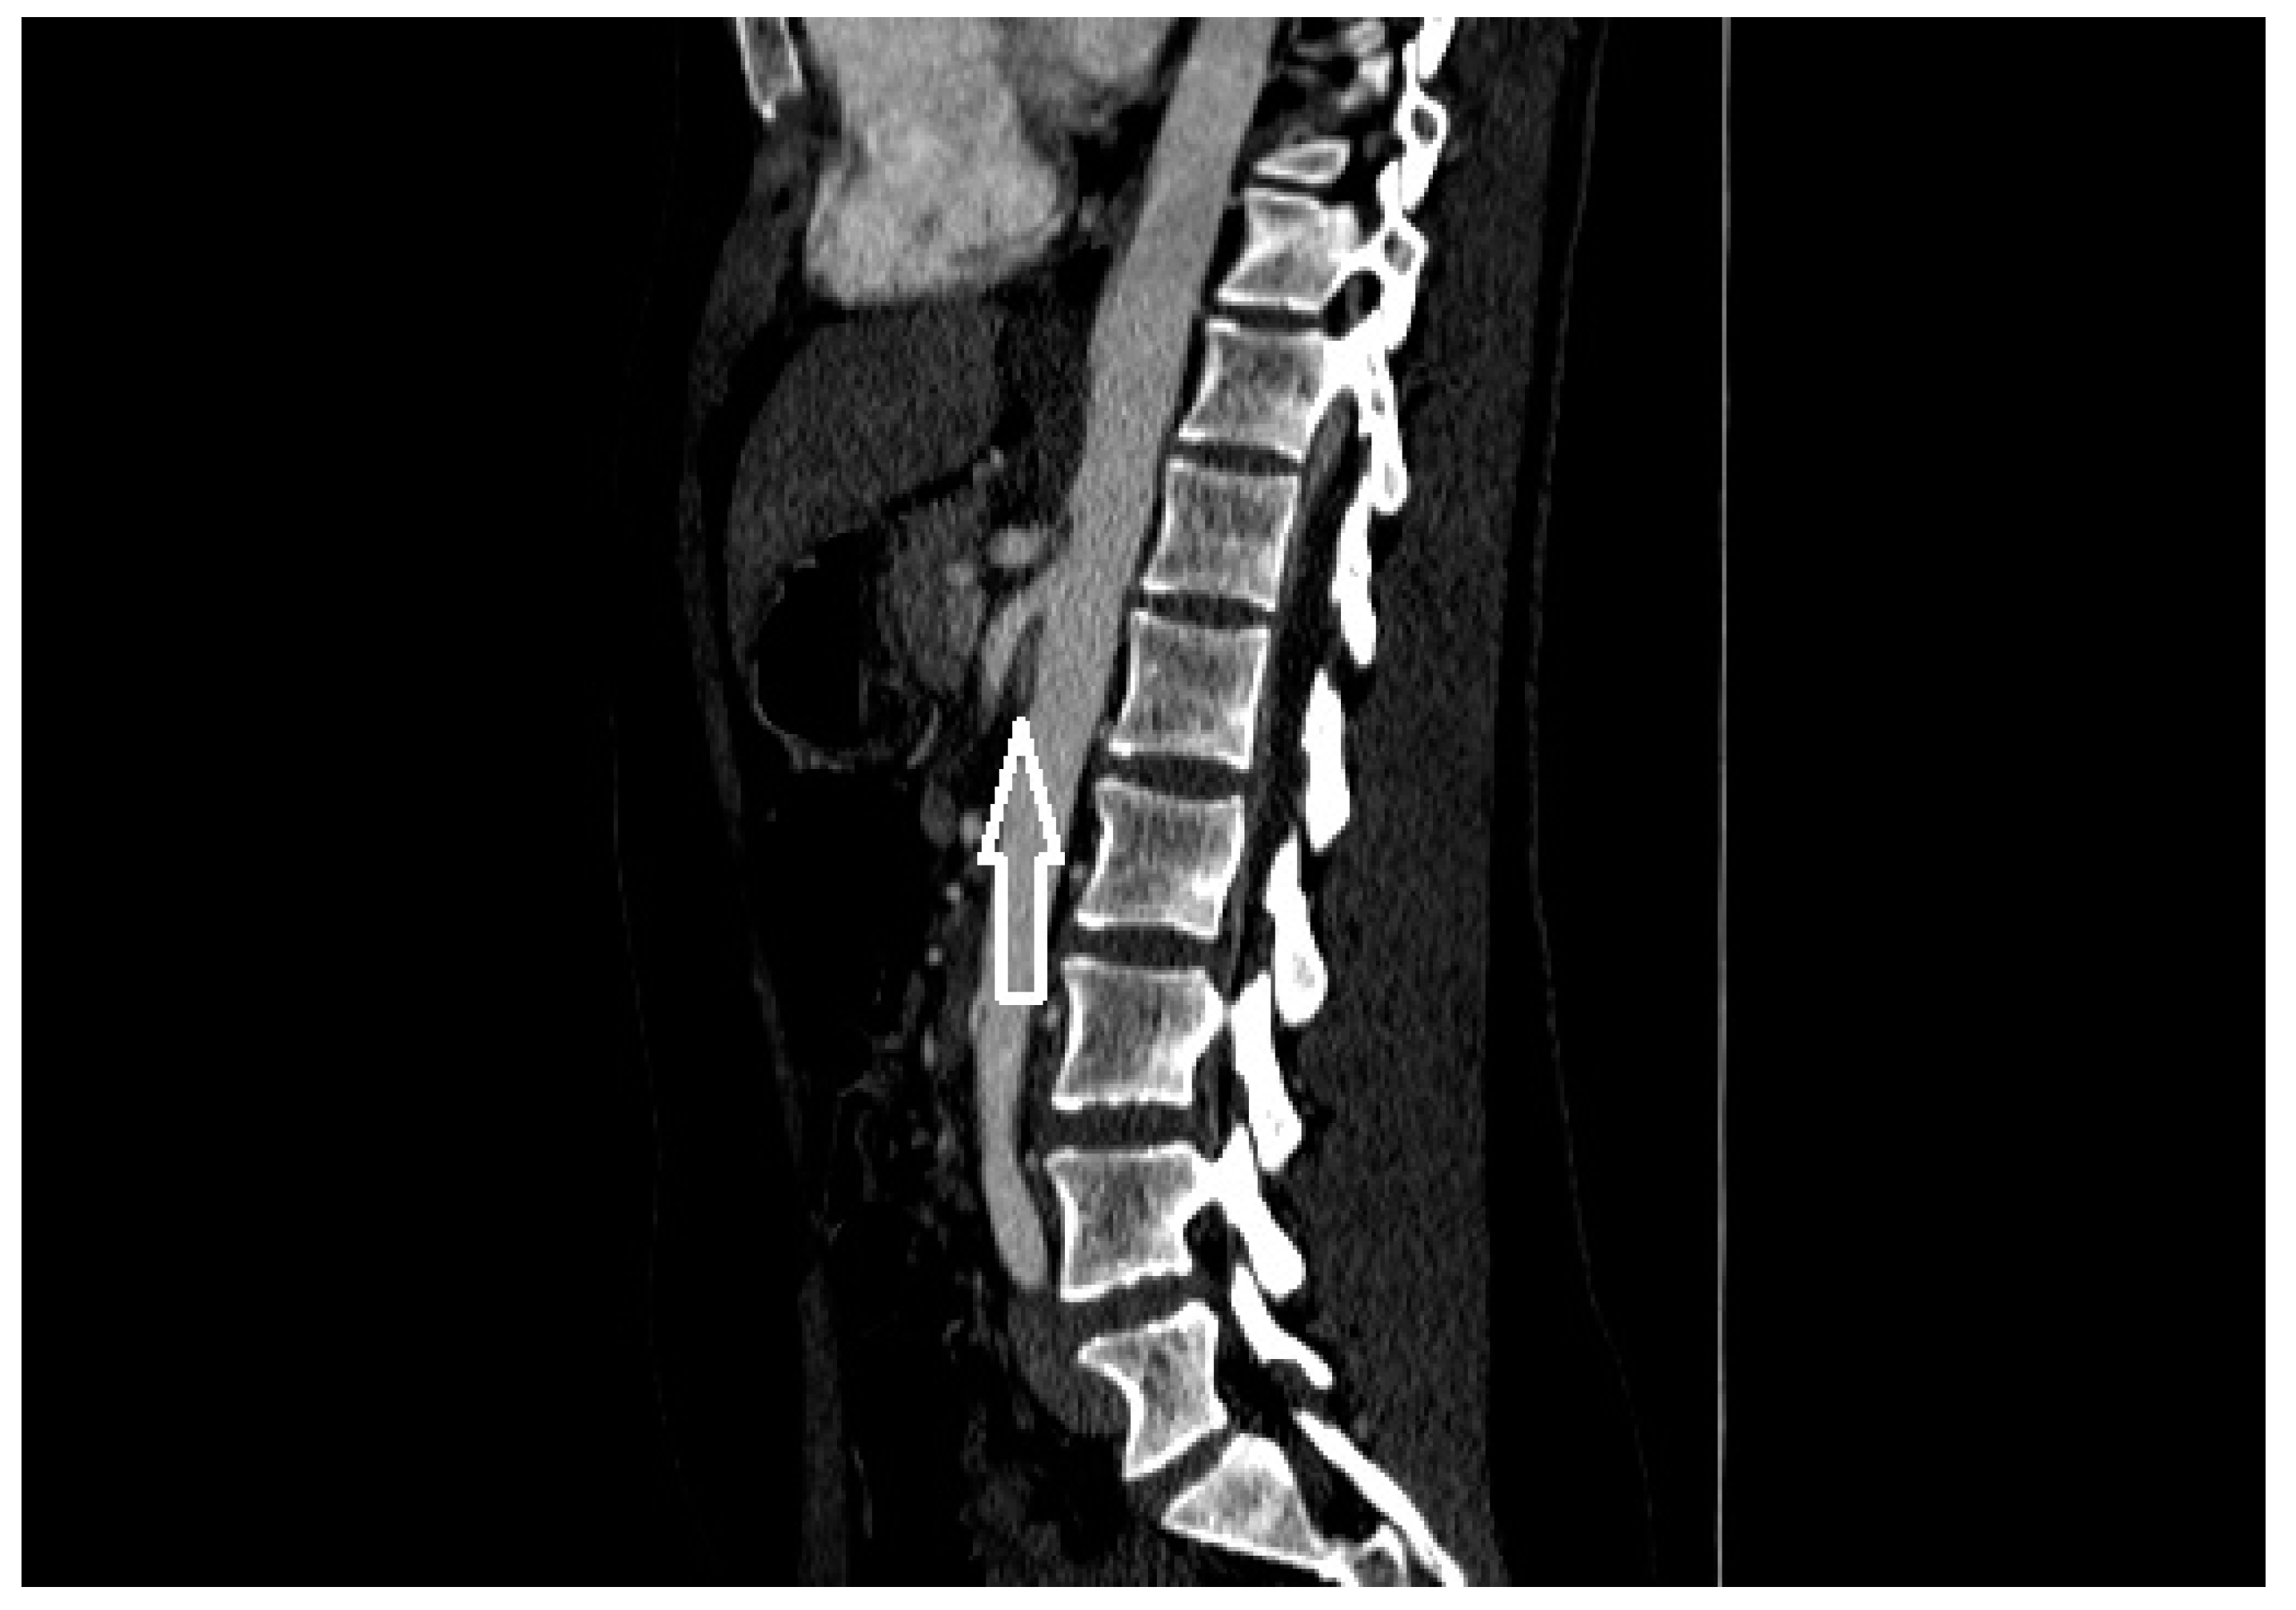

From pubs.rsna.org

CT Angiography of Posterior Nutcracker Syndrome Radiology Nutcracker Syndrome Ct Findings — ncs is a diagnostic consideration in patients with unexplained. nutcracker syndrome (ncs) is an increasingly recognized venous compressive disease. — nutcracker syndrome (ncs) is a syndrome caused by compression of the. Although people with ncs can experience. Nutcracker Syndrome Ct Findings.

CT Angiography of Posterior Nutcracker Syndrome Radiology Nutcracker Syndrome Ct Findings nutcracker syndrome (ncs) is an increasingly recognized venous compressive disease. — nutcracker syndrome (ncs) is a syndrome caused by compression of the. Although people with ncs can experience. — ncs is a diagnostic consideration in patients with unexplained. Nutcracker Syndrome Ct Findings.